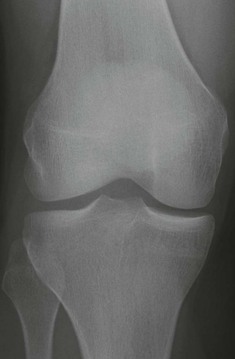

What is varus deformity of the knee?

Varus knee, also known as genu varum, is a condition that affects the alignment of bones in a person's leg. If you have this condition, the larger bone in your calf, the tibia, is misaligned with the larger bone in your thigh, the femur. Varus knee is common in newborns.Nov 30, 2020